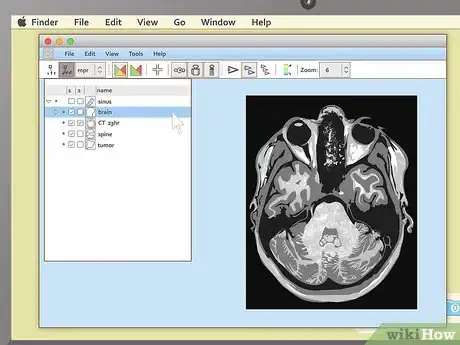

Load the study. Again, the exact steps you'll need to take here can vary slightly depending on the exact program you have packaged with your images. Generally, most MRI viewers will have some sort of option to load or import images that you can select from the menu bar at the top of the screen. In this case, select this option, then pick the image file on your disc that you'd like to look at.

• Note that most medical imaging software refers to collections of images as "studies". You may not see an "import image" option, but you'll probably see something to the effect of "import study."

• Another option you may encounter is that, as soon as the program loads, it will present you with a "table of contents" of all the MRIs on the disc. In this case, simply select the study you want to view first to proceed.

View the images. Most MRI programs start with a large black space on one side of the screen and a smaller toolbar on the other side. If you see small preview pictures of your MRI images in the toolbar, double click on the image you want to view. It should load a large version of the image into the black area.

• Be patient while you wait for your images to load. Though the viewing programs don't usually look like much, a single MRI image contains a large amount of information, so it may take your computer a moment or two to finish the job of loading it up.